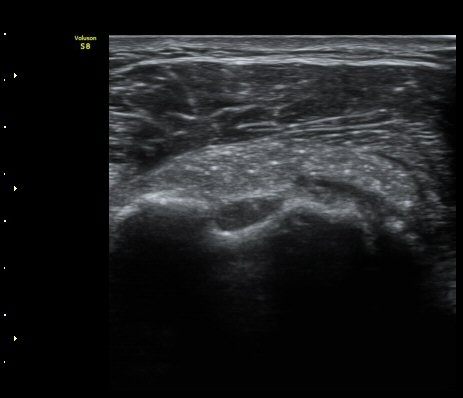

ÁÖ»ç ÈíÀΰú Á¡¾×³¶³» ÁÖ»çÄ¡·á(÷ºÎ ÆÄÀÏ) 1ÀÏ ÈÄ ½ÃÇàÇÑ °Ë»ç¿¡¼­ Á¡¾×³¶ÀÇ ºÎÁ¾ ¹× ¼®È¸ÀÇ

Á¦°Å°¡ °üÂû µÊ(±×¸² 6, 7).